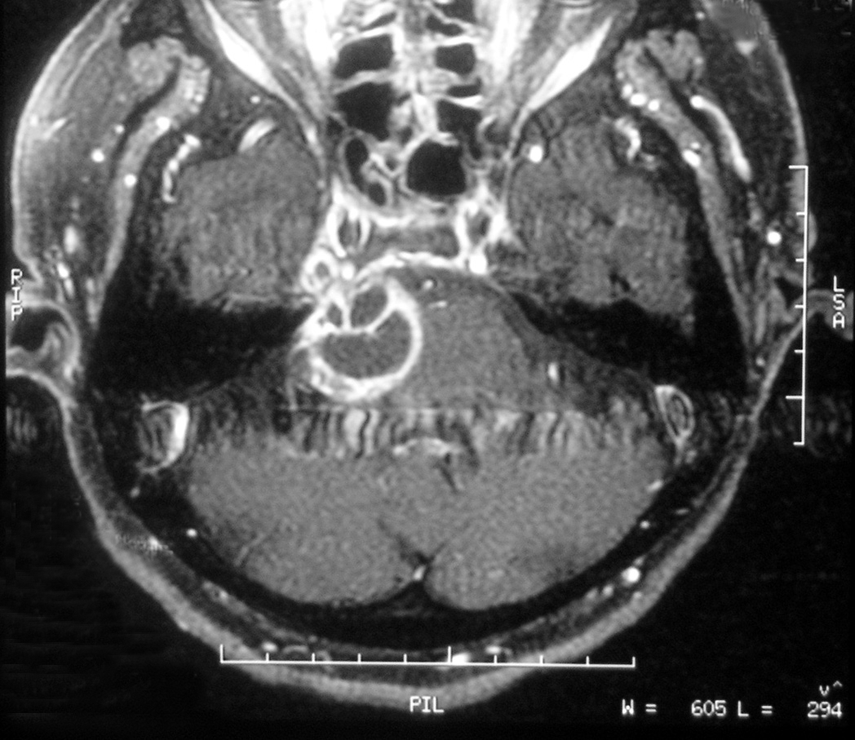

巨大聴神経鞘腫の造影MRI

左小脳橋角部に巨大な腫瘍を認め、脳幹は著明に圧排され第Ⅳ脳室は正中から右に強く変位し変形している(a)。冠状断では側脳室、第Ⅲ脳室の拡大を認め、閉塞性水頭症の存在が示されている(b)。